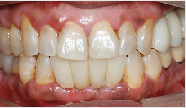

After